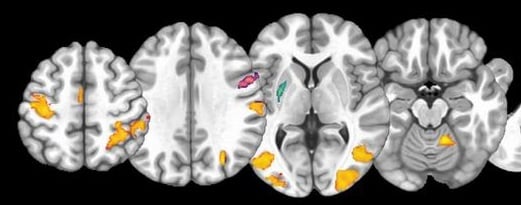

The BRAIN Lab team is seeking individuals 8-35 years old for our studies of brain and behavioral development in autism spectrum disorder (ASD). Individuals with ASD and individuals without ASD may participate. Due to the COVID-19 pandemic, we are currently conducting remote assessments only. If you are interested in participating in our studies*, follow the link above and click on ENROLL IN A STUDY. For more information about study participation, or to learn about the safety procedures being implemented by our research team, contacting us at (785) 864-4461 or brainlab@ku.edu.